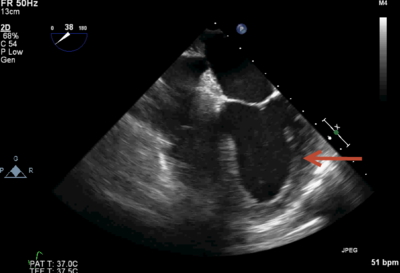

A 74-year-old woman undergoing an exploratory laparotomy and has blood pressure 60/40 mmHg and heart rate of 50 beats per minute. Based on the intraoperative TEE below (which shows severe aortic insufficiency), what would be the MOST appropriate drug to treat her hypotension?

Answer

• 10 mcg of epinephrine

• 50 mcg of nitroglycerine

• 100 mcg of phenylephrine

• 1 unit of vasopressin